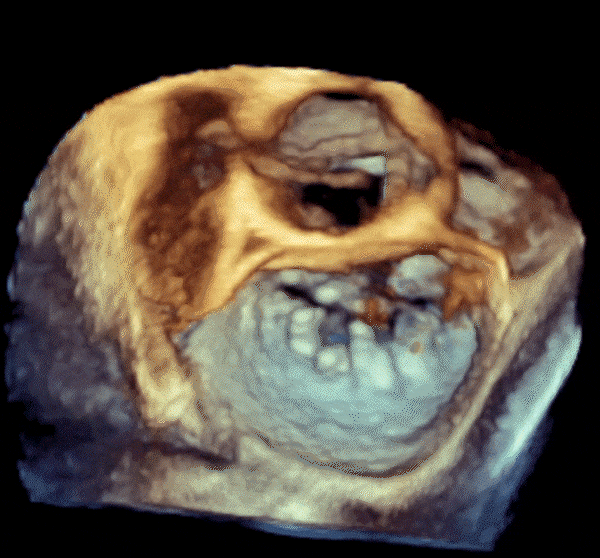

心脏超声示左室增大,二尖瓣2、3区脱垂伴重度反流(腱索断裂),Carpentier分型Ⅱ型,典型Barlow综合征表现;二尖瓣开放面积5.0cm²,3区瓣环内径31mm,前叶长22mm、后叶17mm,前叶收缩期关闭瓣体部分呈拱形突向左房腔,瓣膜游离缘对合欠佳,可见腱索断裂,长度9mm;2区瓣环内径32mm,前叶长22mm、后叶10mm,前后叶均可脱垂;三尖瓣重度反流。CDFI示瓣口重度偏心性反流,反流束沿主动脉后壁走行,肺静脉收缩期可见反向频谱。

综合上述术前评估结果,患者二尖瓣、三尖瓣重度反流合并心功能不全,二尖瓣2区、3区瓣叶大面积脱垂,伴腱索断裂,属偏红区Barlow病变。手术团队商讨后一致决定开展经导管二三尖瓣联合钳夹术,优先处理二尖瓣反流,从内到外依次植入2-3枚NeoNova® C6夹合器,在保证瓣口面积的情况下,最大程度夹持瓣叶组织以有效解决反流。术中需注意防止腱索缠绕,有必要可将夹合器延展至“一字型”状态。

术前3D